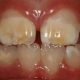

El prognatismo, es una maloclusión de clase III esquelética y se caracteriza por un crecimiento excesivo de la mandíbula inferior respecto al maxilar superior.

Esta situación genera problemas oclusales y en la mastifacación, además de una notable alteracion estética que puede derivar en problemas psicológicos, como falta de autoestima.